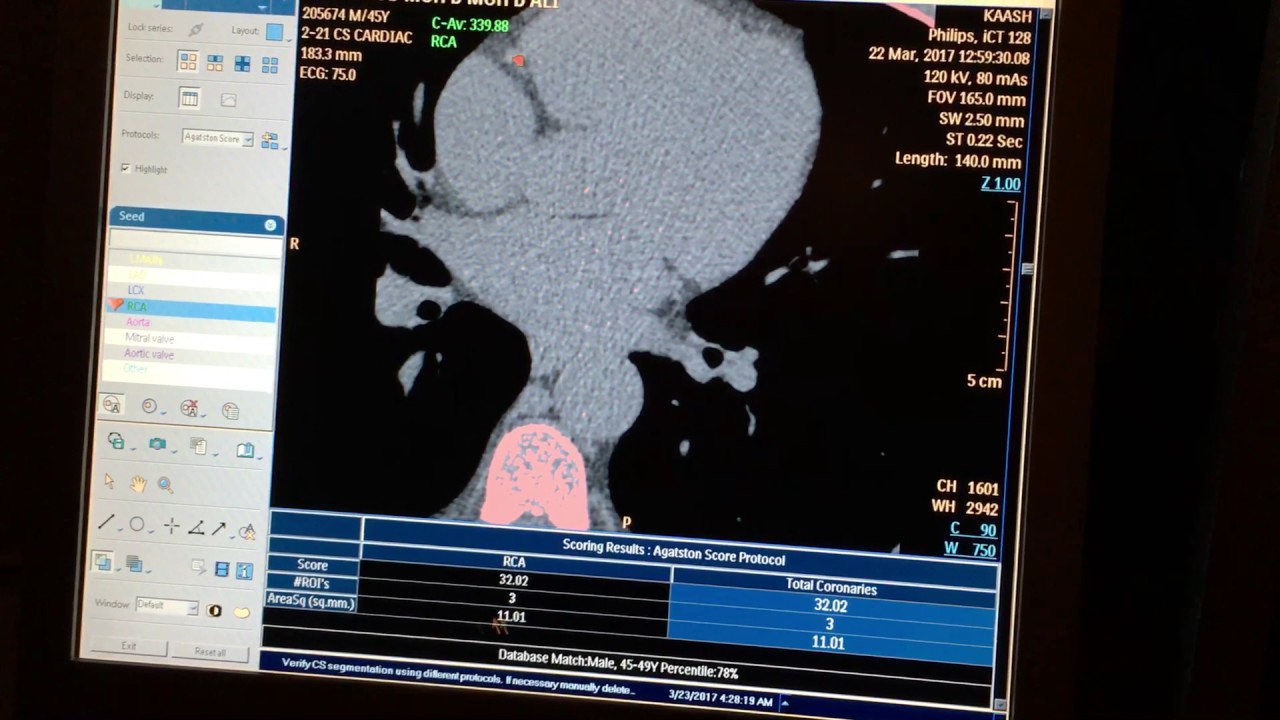

From www.youtube.com

CT Cardiac Calcium Scoring YouTube Ct Cardiac Scoring Promotion how much does a cardiac ct calcium scoring cost? a cac score can potentially be reported from the approximately 7.1 million annual diagnostic noncontrast ct (ncct) examinations performed annually in the united states. in asymptomatic patients without established atherosclerotic cardiovascular disease (ascvd), the. Purchase a cardiac ct calcium scoring today on mdsave. the ct scans your. Ct Cardiac Scoring Promotion.